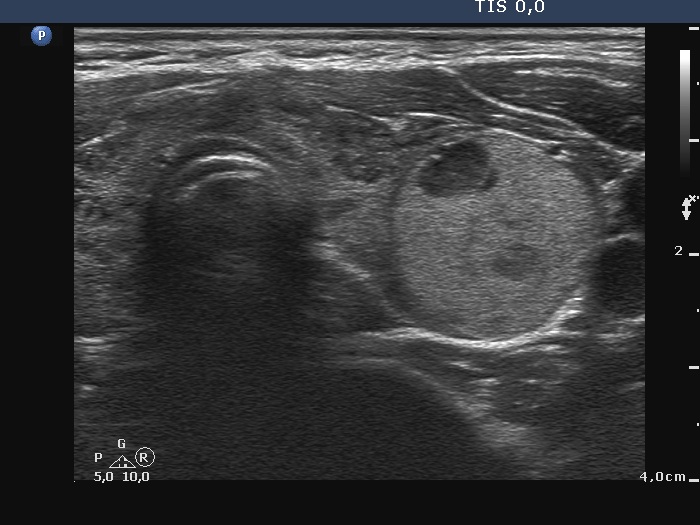

Third examination - seven years after the first examination (third row of images)

Clinical presentation: The patient hasn't been operated on, yet. She came to a repeat examination because of neck complaints, she felt pressure when lying down.

Palpation: a firm nodule in the left lobe.

Laboratory tests: TSH 1.70 mIU/L.

The dimensions of the nodule in the left lobe were 41x25x50 mm, width, depth, length, respectively, the volume of the lesion was 26.8 mL.

FNA resulted in follicular tumor.

Histopathology disclosed minimally invasive follicular cancer. The largest diameter was measured 55 mm. Both capsular and vascular invasions were found microscopically.